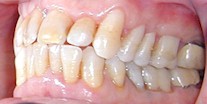

|

ANTES |

Este

paciente tenia problemas de electrogalvanismo entre los diferentes metales

en boca |

DESPUES |

Después de

un tratamiento con criterio biológico se le retiro todas las amalgamas

quedando solo un metal que es el cromoniquel evitando de este modo el

electrogalvanismo |